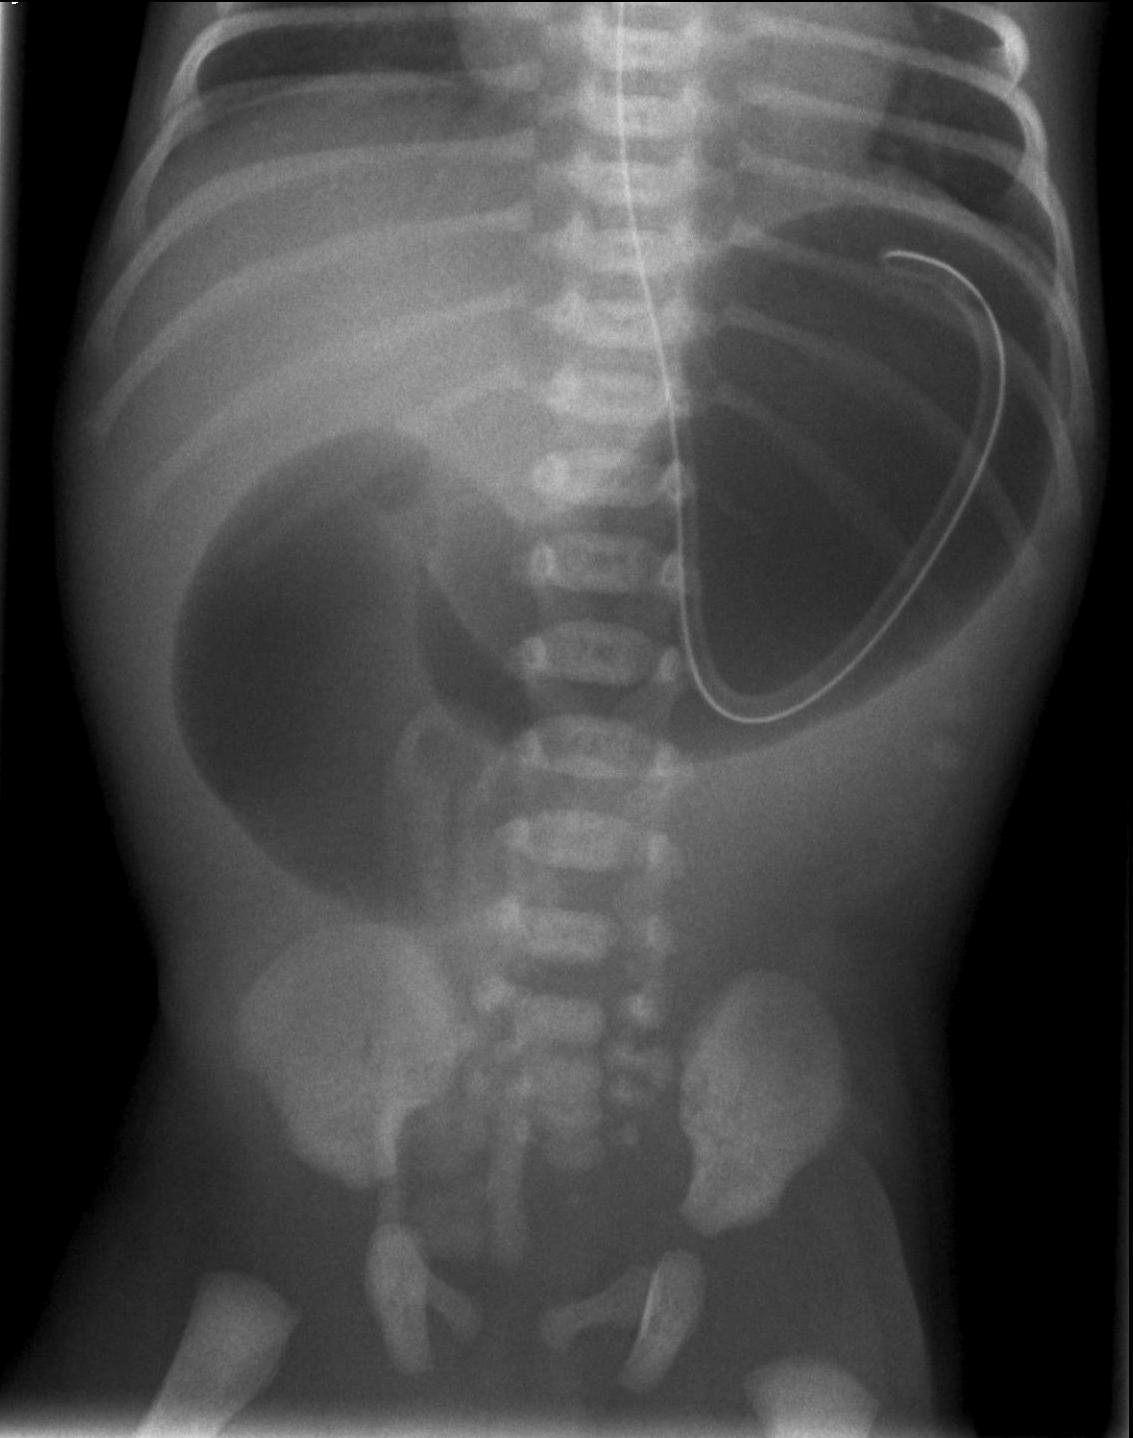

Duodenal obstruction. The cause of proximal obstruction is primarily duodenal atresia or stenosis. Usually US is able to depict the distended stomach and duodenum during intrauterine US examination as a cystic mass, while other intestines are completely free of fluids. Vomiting occurs in the first hours of extra-uterine life. Plain abdominal radiograph in cases of atresia will reveal the so called “double bubble” sign, where the stomach and the duodenum are distended but on distal segments, the intestines are gas free. In cases of stenosis, the distal intestinal loops will also show some air content. Other examinations are unnecessary and air can be used as a negative contrast material.

13. Distended stomach and duodenal bulbus, “Double bubble” sign. Duodenal atresia.